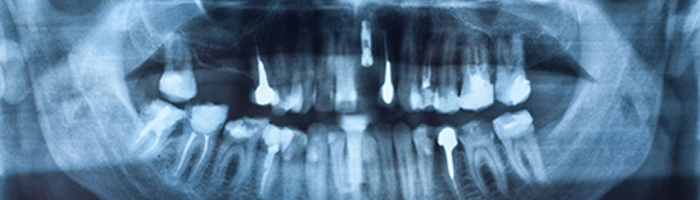

Digitales Röntgen

Bis zu 90% weniger Strahlenbelastung in unserer Zahnarztpraxis - sprechen Sie mit Ihrem Zahnarzt Dr. med. dent. Bosman

In Deutschlands Zahnarztpraxen wird zuviel geröntgt, zu oft und mit zu hoher Strahlenbelastung. Als Konsequenz wurde die Röntgenverordnung überarbeitet. Ein Schritt in die richtige Richtung ist das digitale Röntgen. Diese Technik benötigt nur einen Bruchteil der konventionellen Strahlendosis, kommt ohne Filme, Entwicklungsmaschinen und giftige Chemikalien aus. Sie bietet wesentlich detailreichere und zuverlässigere Aufnahmen.

Mit dem Einsatz digitaler bildaufzeichnender Verfahren wurde 1987 ein ganz neuer Weg beschritten zahnmedizinische Aufnahmen in intraoraler Technik zu erfassen. Röntgenbilder, die mit einer Speicherfolie aufgenommen werden, sind in ihrer Aufnahmetechnik den herkömmlichen, filmbasierten Techniken bis auf das elekronische Entwicklungsgerät ähnlich. Die durch die digitale Technik erzeugten Bilder zeichnen sich durch eine deutliche Reduktion der Strahlenbelastung aus. Die Visualisierung des Röntgenbildes erfolgt am Bildschirm und lässt sich mit Hilfe von Bildbearbeitungsprogrammen nach der Aufnahme korrigieren bzw. optimieren.